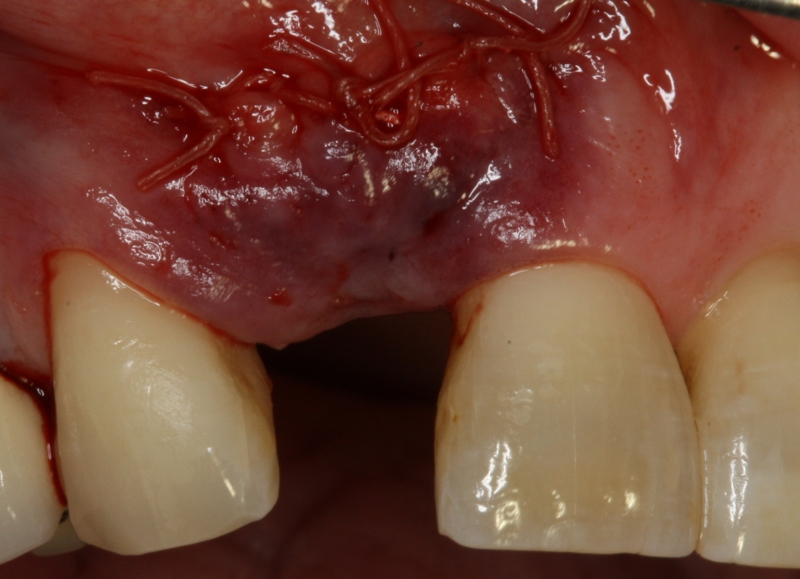

06/20 - Tension-free wound closureGBR with maxresorb® & Jason® membrane - Prof. Dr. Dr. D. Rothamel